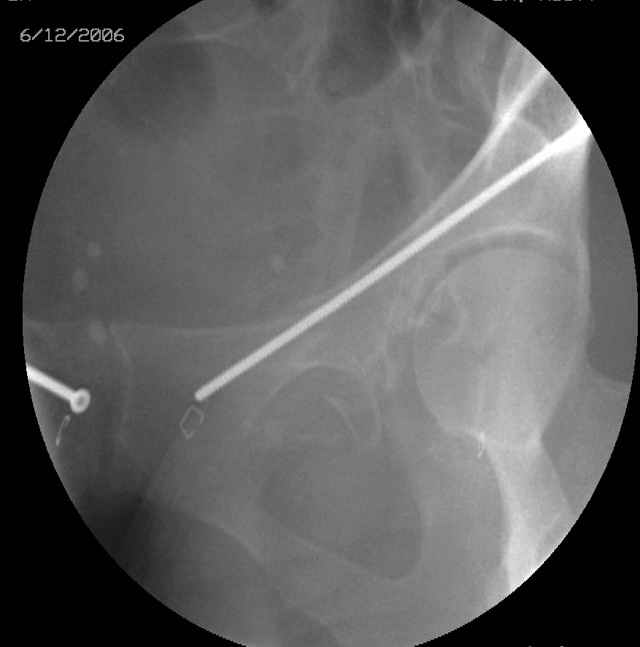

The 2nd example is of a motorcyclist with a transverse fracture-dislocation...he had a closed attempted reduction and placed in traction but the manipulative reduction was not concentric (not unusual for this injury pattern)...so the traction was adjusted to be just enough to disengage the head from the fracture (12#) until he could be cleared for surgery one day after injury...he was treated "urgently" then with a prone KL, clean the fracture, reduce and clamp it, screw it, support with a balanced plate, close, and enjoy...2-3hours, 400cc EBL, blah, blah, blah..

Here's a pic from the foot of the bed and you can see the clamp in the wound and the knee is extended so he must've had a tight rectus. The C-arm is rolled back to an obturator oblique image to reveal the anterior column...we put a slight outlet tilt to combine the images and give a better view of the anterior column...we can see the posterior column limb reduction in the wound, we can palpate the quadrilateral surface limb, and the image demonstrates the anterior column portion...you can adjust the tilt and rotation to image tangentially to the fracture plane if you'd like. We've inserted a 2mm K wire to site the starting point and aim/orientation for the drill and screw

Prone Inlet

OK, now we're inserting the drill percutaneosuy using a sleeve. This fluoro shot is not for this patient (notice no clamp) but I was too lazy to go searching the PACS for one with the clamp on, so pretend...I'll save the next ones and send along...the imaging is the same and the clamp doesn't obstruct imaging other than very rarely...you can always tilt the C-arm a bit to clear it if the clamp obstructs the exact spot that you'd like to see. We'll assume that everyone knows the safe zone for a medullary ramus screw. Use a calibrated drill and sleeve of known length to simplify your life...or use Alex's fancy cannulated screws...I like 3.5mm screws because the oscillating 2.5mm drill bounces and remains intraosseus when it oscillates and contacts endosteal cortical ramus... so will the screw, and like a long bent screw IF the fracture is clamped... if unclamped, when the screw contacts the endosteum, it pushes the reduction apart instead of bouncing. The big 7mm cannulated screws fit few patients and extrude...we very rarely use them any more...you'll see an old one later.

Prone Obturator-Outlet

Screw insertion using the obturator-outlet combination image.

12.Prone Obturator-Outlet

Same with a contoured pelvic reconstruction plate applied and tensioned.

Prone Iliac Oblique

The other oblique reveals the extra-articular implants.... you know the AC screw is extra-articular from the other views.